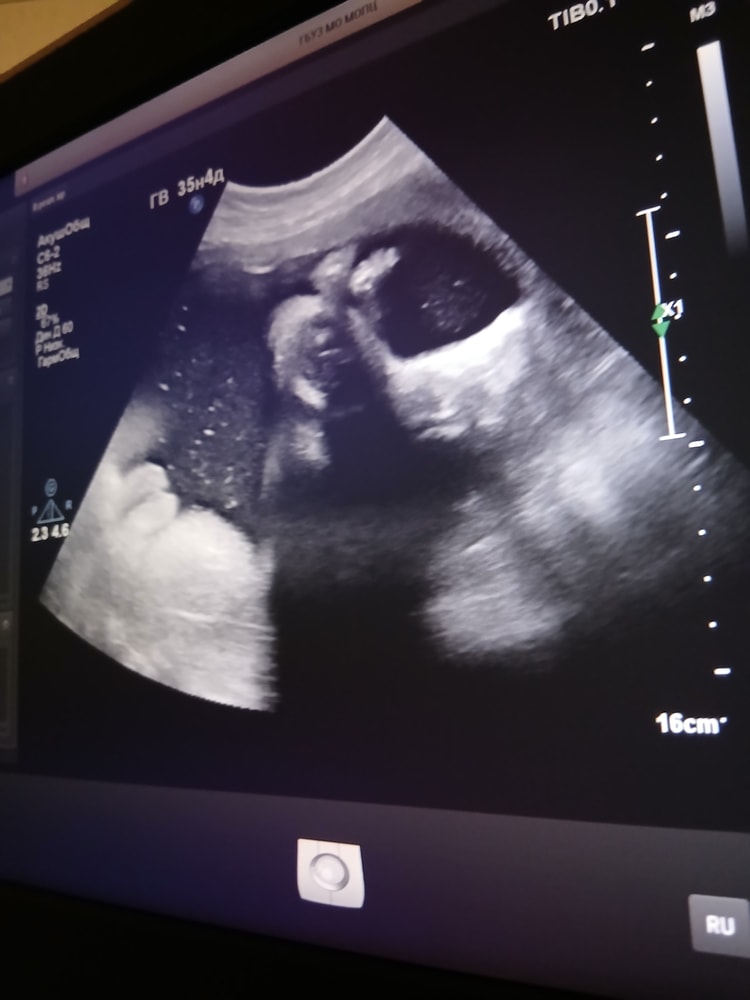

Младшенькая Виктория 14.10.25(35,0)

УЗИ, КТГ, доплерХодила на контрольное узи,многоводие таки осталось ИАЖ 250мм,ожидаемо если честно,во все беременности оно было,удивительно, что в этот раз оно только в 3 триместре появилось, а не как обычно во втором),по весу ставят 2865г +- 427г,самый маленький гномик из всех,может испытаю удачу и попробую родить не крупного ребёнка. Хотя и младшую уже прировняли к крупному плоду,хотя как по мне,это мало))

Ну и как же без фото))

Осторожно,одно из них 18+)))

Алёна , ахахаха,на нижней фотке в нижнем левом углу,варенички видны😅